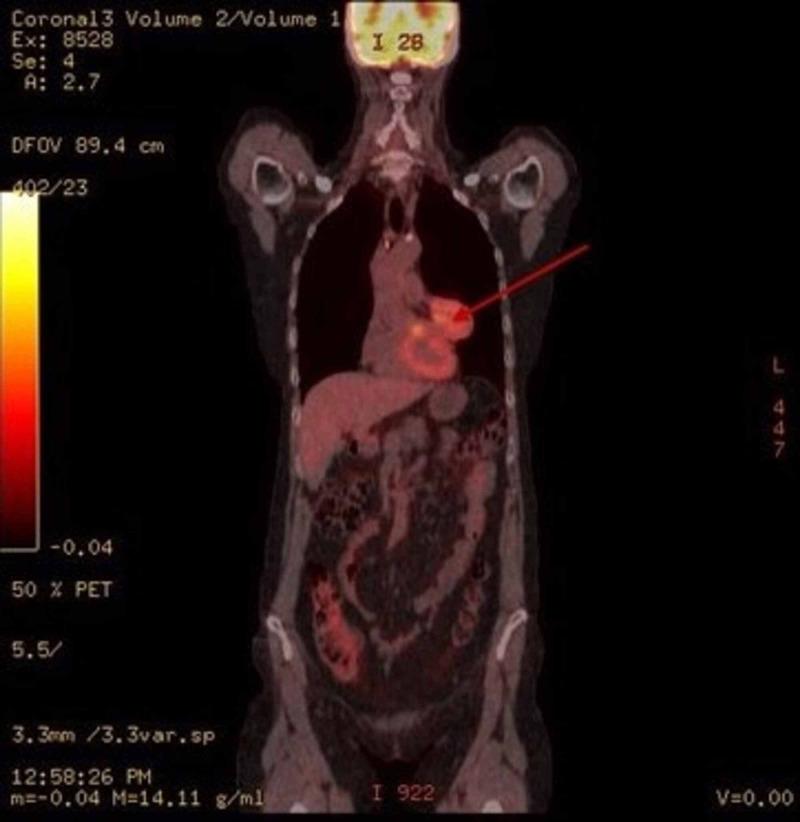

We present a unique case of a satellite pleural-based thymoma. The patient is a 66-year-old Caucasian female with a history of a left pericardial soft tissue mass. She had been asymptomatic. Chest radiograph incidentally revealed an acute increase in the size of the mass. CT scan identified a 5.6 X 5.2 X 4.2 cm mediastinal mass in the left infrahilar region along the left lateral pericardium. Positron emission tomography (PET) scan showed the mass had an increased F18 FDG uptake with standardized uptake value (SUV) of 7.2. Left thoracotomy resected a 81g, 6 X 5.5 X 5.0 cm tan-pink well-encapsulated pedunculated mass displacing the left phrenic nerve. The mass was under the parietal pleura and not attached to the pericardium. Immunohistochemical profile identified the tumor as a thymoma, B1 type. Thymomas are relatively rare in the United States, pleural-based thymomas even more so. Early detection of thymomas is critical to avoid late-stage growths. Pericardial involvement of thymomas increases risk of pericardial effusion, tamponade and a complicated thymectomy. Pleural-based thymomas can result in diaphragmatic paralysis secondary to phrenic nerve involvement.

我们报告一例罕见的胸膜型胸腺瘤病例。患者为66岁的白种女性,有左侧心包软组织肿块病史。她之前并无症状。胸部X光片偶然发现肿块大小急剧增加。CT扫描在左肺门下部区域沿左侧心包发现一个5.6×5.2×4.2cm的纵隔肿块。正电子发射断层扫描(PET)显示该肿块F18 FDG摄取增加,标准化摄取值(SUV)为7.2。左胸切开术切除了一个81g、6×5.5×5.0cm的棕粉色、包膜完整的带蒂肿块,该肿块推移了左侧膈神经。肿块位于壁层胸膜下方,未附着于心包。免疫组织化学分析确定该肿瘤为B1型胸腺瘤。胸腺瘤在美国相对少见,胸膜型胸腺瘤更为罕见。胸腺瘤的早期发现对于避免晚期生长至关重要。胸腺瘤侵犯心包会增加心包积液、心脏压塞和复杂胸腺切除术的风险。胸膜型胸腺瘤可导致因膈神经受累继发的膈肌麻痹。